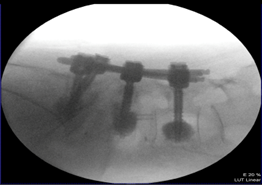

病例示範:

一位65歲女性因為第四腰椎至第一薦椎滑脫導致脊管狹窄及神經壓迫,經臨床影像學診斷證實後,需要進行脊椎減壓手術及骨融合植釘固定手術,到烏日林新醫院求診,手術以最新的免術前電腦斷層的電腦導航進行手術,手術後狀況良好,術後第三天就可以穿戴背架下床活動。

圖:脊椎電腦輔助手術導航